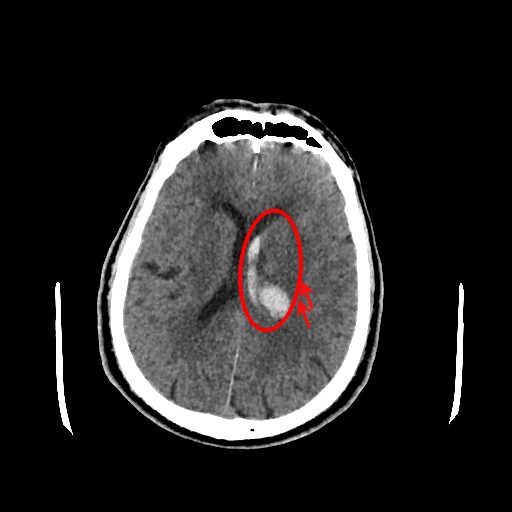

Figure 1: Illustrative examples of different types of brain hemorrhages in CT scans. The hemorrhagic regions are highlighted in red. (a) IPH, (b) IVH, (c) EDH, (d) SAH, (e) SDH.

The dataset used in this study was collected from two medical centers in Tehran, Iran: Rasoul Akram Hospital and Firouzabadi Hospital, over a period spanning 2018 to 2024. All CT scans were manually labeled hierarchically by two board-certified neurosurgeons to ensure accurate classification of ICH subtypes. The labeling process involved an initial annotation by one neurosurgeon, followed by validation and verification by a second expert to minimize errors and inconsistencies. Fig. 1 illustrates representative examples of different ICH subtypes in brain CT scans. The hemorrhagic regions are highlighted in red for better visualization. These annotated examples provide insight into the distinct imaging characteristics of each hemorrhage type, emphasizing the variability in their locations and appearances within the brain. The study received ethical approval, and data collection was conducted in compliance with institutional review board (IRB) regulations and the Declaration of Helsinki, ensuring patient confidentiality and adherence to ethical standards.